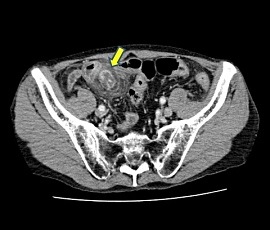

急性腹症にて救急受診。CT検査にて、下腹部正中右側の回腸遠位部に腸管壁肥厚と周囲の脂肪織濃度上昇および微小な遊離ガス像を認め、内部に嚢胞性病変を認めた。精査の結果、メッケル憩室炎、穿孔と診断。緊急手術(腹腔鏡下小腸切除術手術(単孔式))を施行した。

CT画像